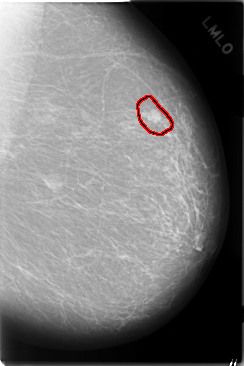

C_0025_1.RIGHT_MLO

FILE: C_0025_1.LEFT_MLO.OVERLAY

TOTAL_ABNORMALITIES 1

ABNORMALITY 1

LESION_TYPE MASS SHAPE OVAL MARGINS CIRCUMSCRIBED

ASSESSMENT 4

SUBTLETY 5

PATHOLOGY MALIGNANT

TOTAL_OUTLINES 1

BOUNDARY

LEFT_MLO LINES 5848 PIXELS_PER_LINE 3904 BITS_PER_PIXEL 12 RESOLUTION 50 OVERLAY